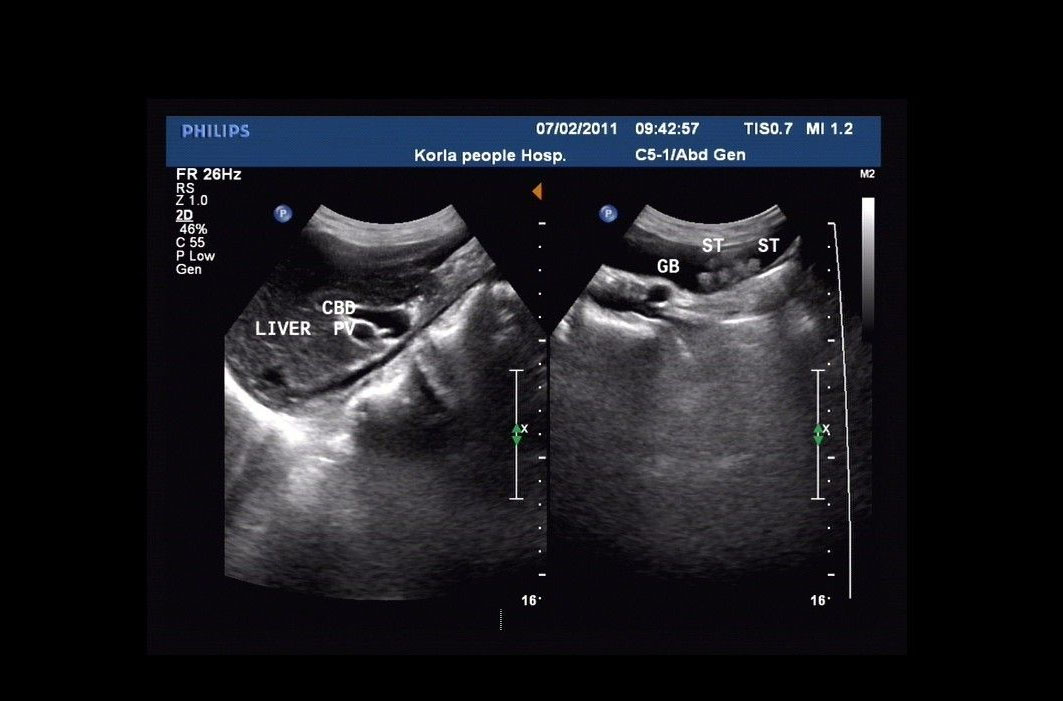

患膽結(jié)石需做超聲檢查

患膽結(jié)石需做超聲檢查,因需要了解結(jié)石的數(shù)量、形態(tài)、大小以及位置、膽囊管和頸部的變化,需要腹腔鏡手術(shù)的病例需要了解膽囊三角的相關(guān)變化;需要注意有無阻塞和并發(fā)癥,膽囊壁厚度變化,膽囊周圍變化,無聲影結(jié)石和膽囊占位的區(qū)別等等。老年人即便發(fā)生膽囊結(jié)石頸部或膽囊管嵌頓、膽囊炎化膿穿孔等改變,也會由于癥狀不典型、描述不確切、想挺挺就過去了而耽誤最佳和相對簡單的治療期。